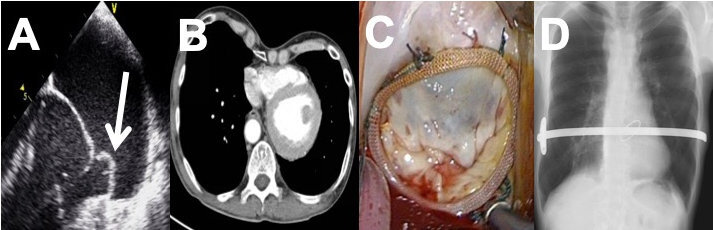

This case study describes the successful short-term outcome of staged minimally invasive pectus excavatum correction and endoscopic mitral valve repair in a patient with severe mitral valve regurgitation and pectus excavatum.